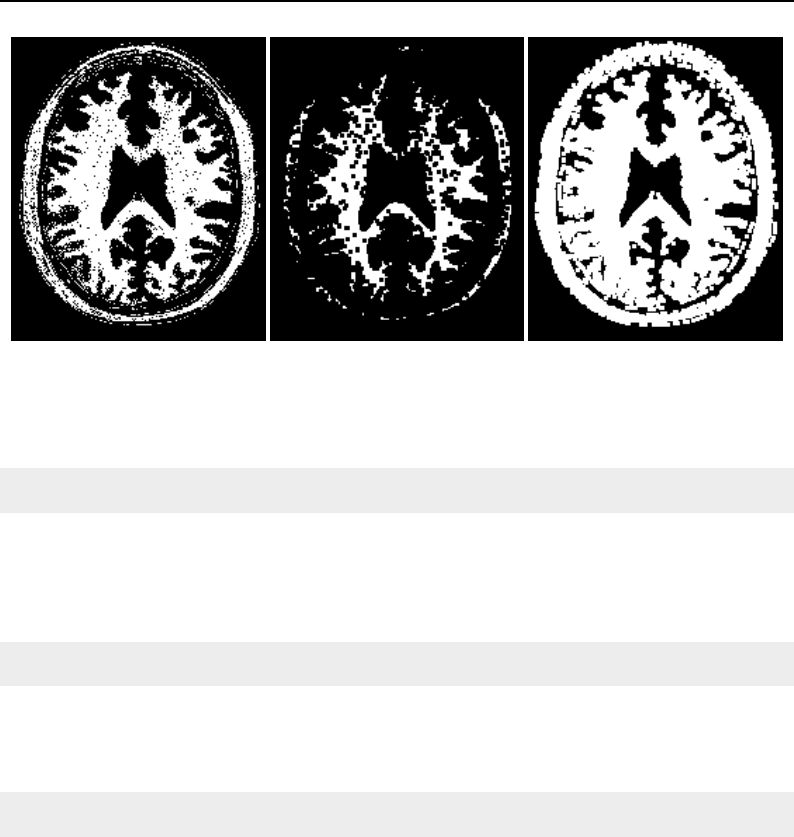

The National Library of Medicine Insight Segmentation and Registration Toolkit, shortened as the

Insight Toolkit (ITK), is an open-source software toolkit for performing registration and segmenta-

tion. Segmentation is the process of identifying and classifying data found in a digitally sampled

representation. Typically the sampled representation is an image acquired from such medical instru-

mentation as CT or MRI scanners. Registration is the task of aligning or developing correspondences

between data. For example, in the medical environment, a CT scan may be aligned with a MRI scan

in order to combine the information contained in both.